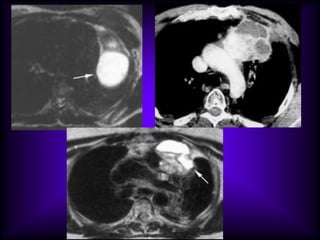

Mediastinal Cysts

The CT features of benign

mediastinal cyst are

(a) a smooth, oval or tubular mass with a well-

defined thin wall that usually enhances after

intravascular administration of contrast

material,

(b) homogeneous attenuation, usually in the

range of water attenuation (0–20 HU),

(c) no enhancement of cyst contents, and

(d) no infiltration of adjacent mediastinal

structures.

Cysts that contain serous fluid typically have

long T1 and T2 relaxation values, which

produce low signal intensity on T1-weighted

MR images and high signal intensity on T2-

weighted images.

Because cysts containing nonserous

fluid can have high attenuation at CT,

they may be mistaken for solid

lesions. MR imaging can be useful in

showing the cystic nature of these

masses because these cysts continue

to have characteristically high signal

intensity when imaged with T2-

weighted sequences regardless of the

nature of the cyst contents